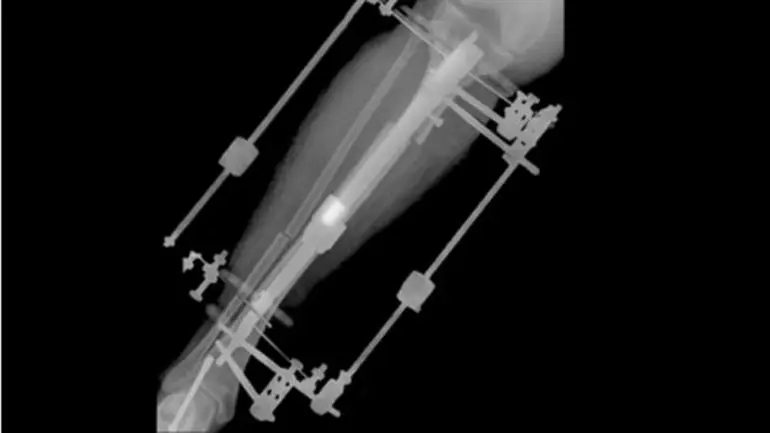

Tras fracturarle el hueso de la tibia en dos lugares, le colocaron dos aparatos fijadores externos unidos al hueso mediante dos tornillos largos. Al cabo de cinco meses, había crecido 5,5 centímetros.